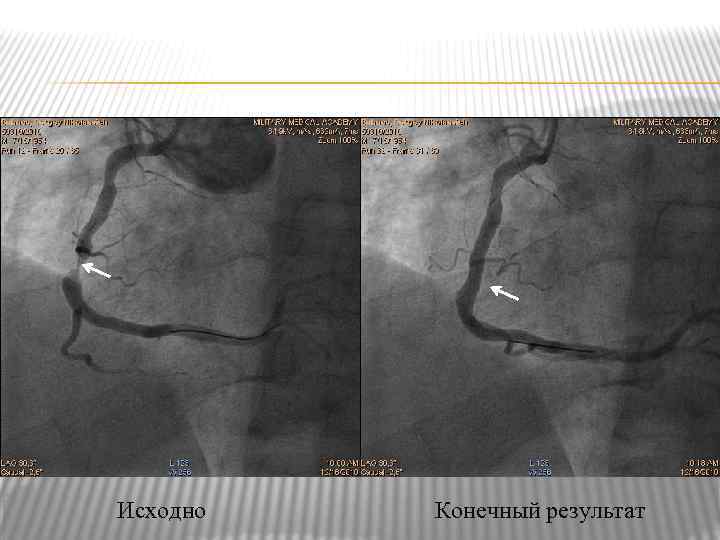

Эндоваскулярные вмешательства при ИБС Субокклюзия ПКА, проведение и имплантация коронарного стента

Эндоваскулярные вмешательства при ИБС Субокклюзия ПКА, проведение и имплантация коронарного стента

Исходно Конечный результат

Исходно Конечный результат